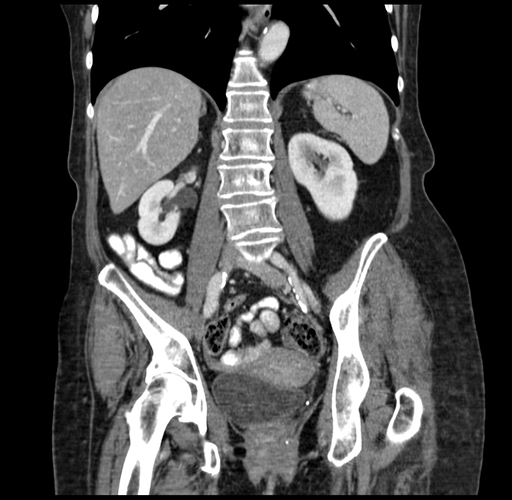

Pre-Chemo: Coronal Venous

Coronal Venous